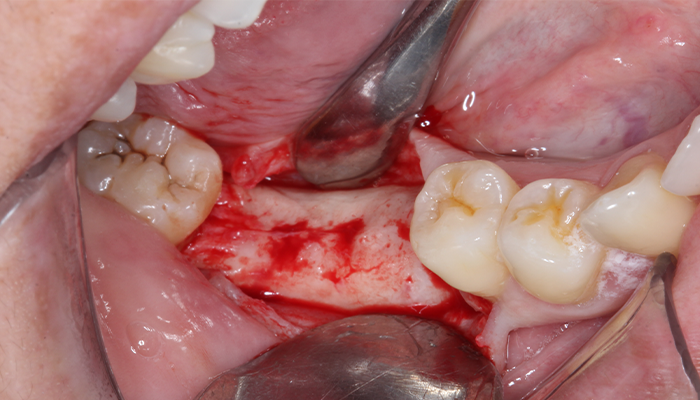

Após uma profilaxia a paciente foi submetida a anestesia local infiltrativa, retalho de espessura total e foi fresado com uma única broca com limitador de profundidade de 13 mm. Após foi conferida a posição das fresa gens com parelelizadores para posterior insta lação dos implantes. Os implantes Aikkon (3,8 × 11 mm) foram instalados 2 mm infraósseos. O torque de instalação foi de 40 N.cm (47), 60 N.cm (46) e 80 N.cm no (36). Como o torque alcançado permite a carga imediata como planejado já foram instalados os intermediários. Foi instalado o pilar Aikkon no 36 com 2,5 mm de altura de transmucoso e dois mini pilares Aikkon de altura de transmucoso 2,5 mm nos implantes 46 e 47.

4 | Retalho de espessura total.